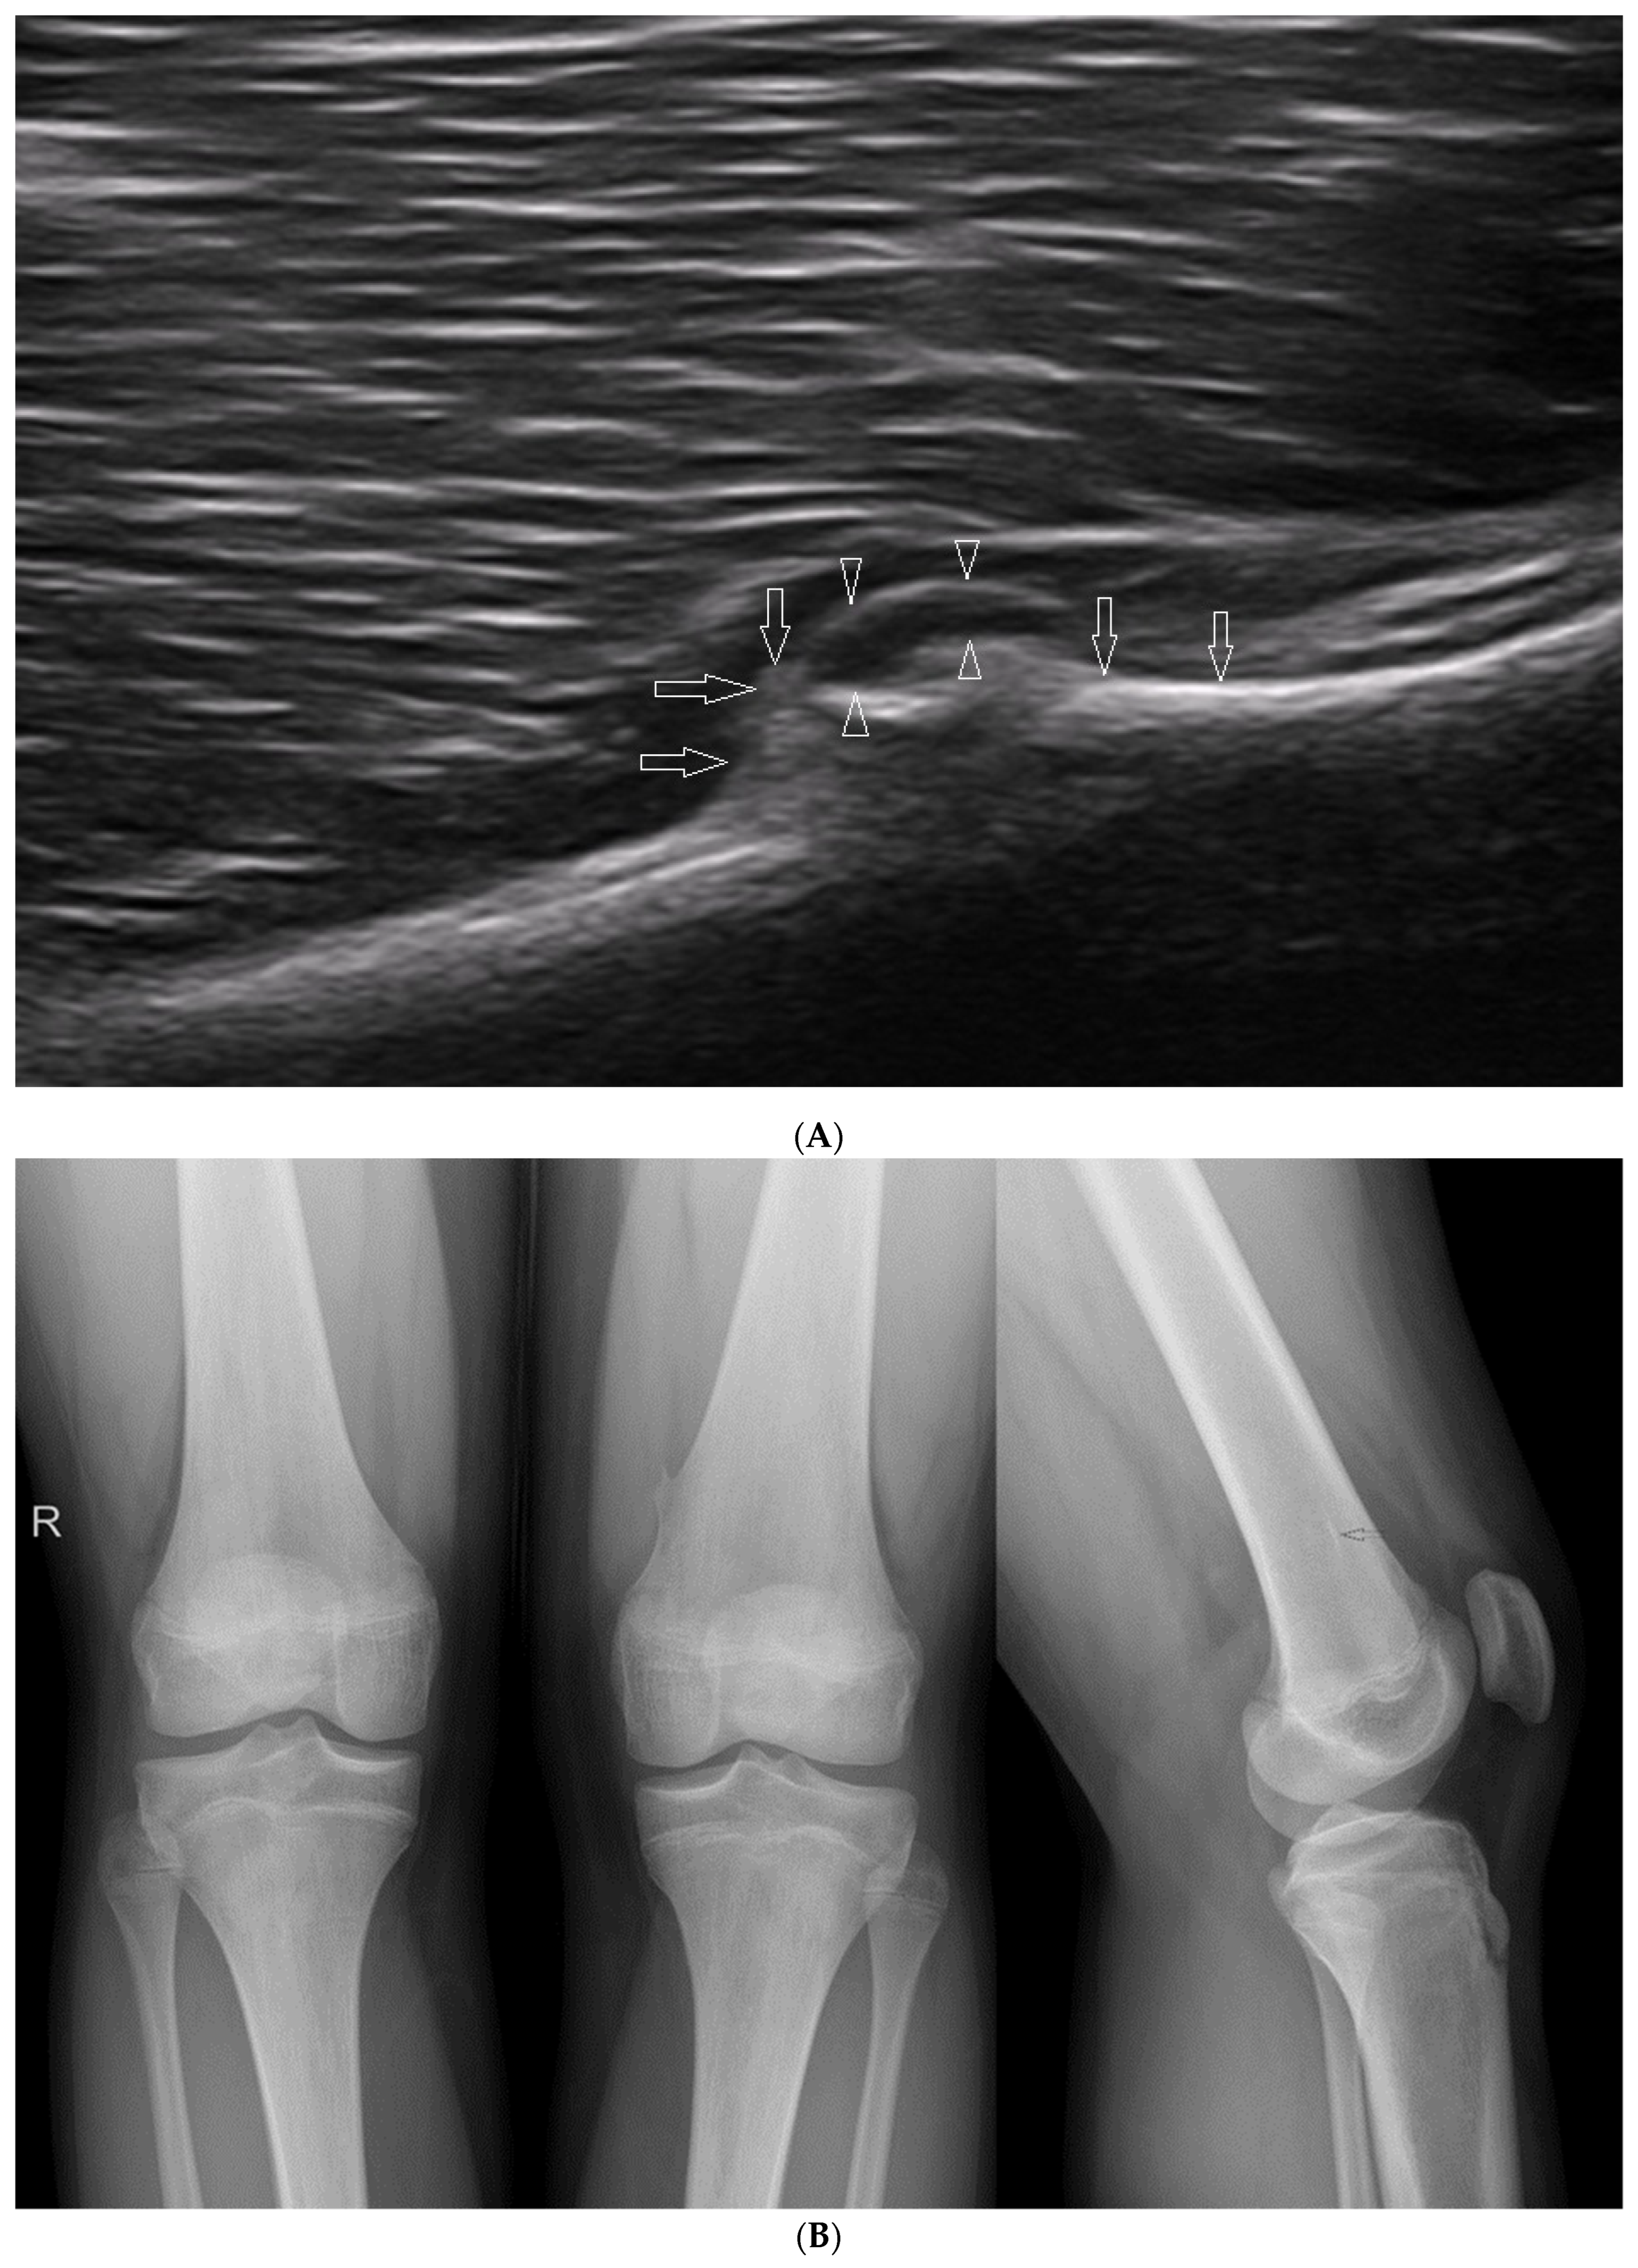

3.2.1. Osteochondritis Dissecans

3.2.2. Osgood–Schlatter Disease